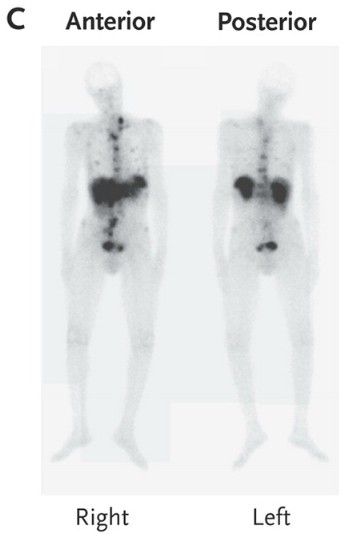

嗜铬粒蛋白A含量升高,为765ng/mL(正常值范围:19.4-98.1)。24小时尿中的5-羟基吲哚乙酸含量升高,为1524μmol(正常值范围:2.5-50.0)。用铟111标记的喷曲肽闪烁显像提示肝和中轴骨转移(图C)。